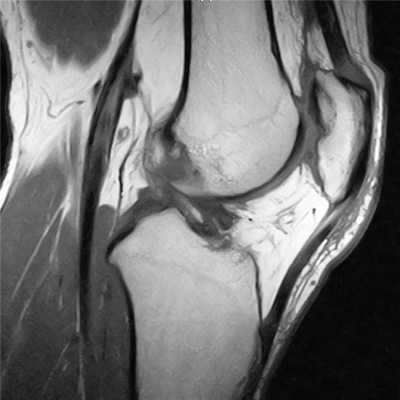

МРТ коленного сустава. Сагиттальная МРТ, отражающая протонную плотность. Нормальная послеоперационная потеря контура сустава.

МРТ коленного сустава. Сагиттальная Т2-взвешенная МРТ. Повторный разрыв оперированного мениска.

После восстановления передней крестообразной связки (ПКС) важно оценить по МРТ ее состоятельность в поддержании стабильности коленного сустава, послеоперационные повреждения структур коленного сустава, оценить послеоперационные контракты в связи с фиброзом и импинджментом. Чаще всего для восстановление целостности ПКС используется аутотрансплантация. Ход костных тоннелей в дистальной части бедренной кости и проксимальном отделе большеберцовой кости имеют решающее значение для правильного функционирования трансплантата ПКС , и важно, чтобы при МРТ коленного сустава оценить положение этих туннелей. Правильное положение бедренного туннеля имеет решающее значение которое позволяет сохранять постоянную длину и натяжение трансплантата при сгибании и разгибании коленного сустава. Если бедренный туннель расположен слишко кпереди это будет вызывать удлинение трансплантата и приводить к нестабильности коленного сустава. Положение бедренного туннеля должно соответствовать задней межмыщелковой крыше на сагиттальных МРТ коленного сустава. На коронарных МРТ коленного сустава, бедренный туннель должен быть на 11 часов для правого коленного сустава и 1 час для левого коленного сустава. Правильное положение большеберцового туннеля важно для предотвращения соударений трансплантата. Положение большеберцовой туннеля должно быть параллельно, но позади склона межмыщелковой крыши (линии Blumensaat), что видно на сагиттальных МРТ. На корональных МРТ, большеберцовый туннель должен открываться на межмыщелковом возвышении. Интактные трансплантаты имеют либо низкую интенсивностью сигнала или промежуточную интенсивность сигнала на Т1-взвещенных МРТ коленного сустава. На Т2-взвешенных МРТ, в трансплантате могут быть участки с промежуточной интенсивностью сигнала, но не должно быть никакого жидкостного сигнала, проходящего через всю толщину трансплантата.Поскольку оба неповрежденные и порванные трансплантаты ПКС могут иметь промежуточную интенсивность сигнала на Т1-взвешенных МРТ коленного сустава, результаты визуализации на T2-взвешенных МРТ имеют решающее значение для выявления нарушения трансплантата. На Т2-взвешенных МРТ не должно быть разрушения трансплантата в виде увеличение интенсивности сигнала. Потеря разгибания или контрактура сгибания является осложнением функции после реконструкции ПКС, который обычно вызвано соударениями (импинджмент) или локальным передним фиброзом. Клинически трудно провести различие между этими двумя состояниями, но каждый из них имеет отличительные черты при МРТ. Соударения наиболее часто происходят, когда туннель большеберцовой кости расположен впереди пересечении склона межмыщелковой крыши с проксимальным отделом большеберцовой кости. Как обсуждалось ранее, большеберцовый туннель должен быть полностью позади пересечении межмыщелковой крыши и большеберцовой кости. МРТ коленного сустава позволяет визуализацировать большеберцовый туннель и его отношение к линии Blumensaat и отношение трансплантата ПКС к межмыщелковой крыше. Локальный передний фиброз - вторая важная причина потери функции разгибания. Он представляет собой локальное поражение, которое находится кпереди от трансплантата ПКС и может быть к его дистальной части. Это участок фиброза захватывается между бедром и голенью, когда колено разгибается, что приводит к механическому блокаде разгибания. Патогенез локального переднего фиброза является неясным. На T1-взвешенных МРТ коленного сустава участок поражения низкой интенсивности сигнала, который расположен кпереди от трансплантата в межмыщелковой выемке. На Т2-взвешенных МРТ коленного сустава, фиброз неоднородный, но преимущественно низкой интенсивности сигнала и хорошо дифференцируется от высокого сигнала суставной жидкости.

МРТ коленного сустава. Сагиттальная Т1-взвешенная МРТ. Нормальный ход трансплантата ПКС.

МРТ коленного сустава. Сагиттальная Т2-взвешенная МРТ. Разрыв трансплантата.